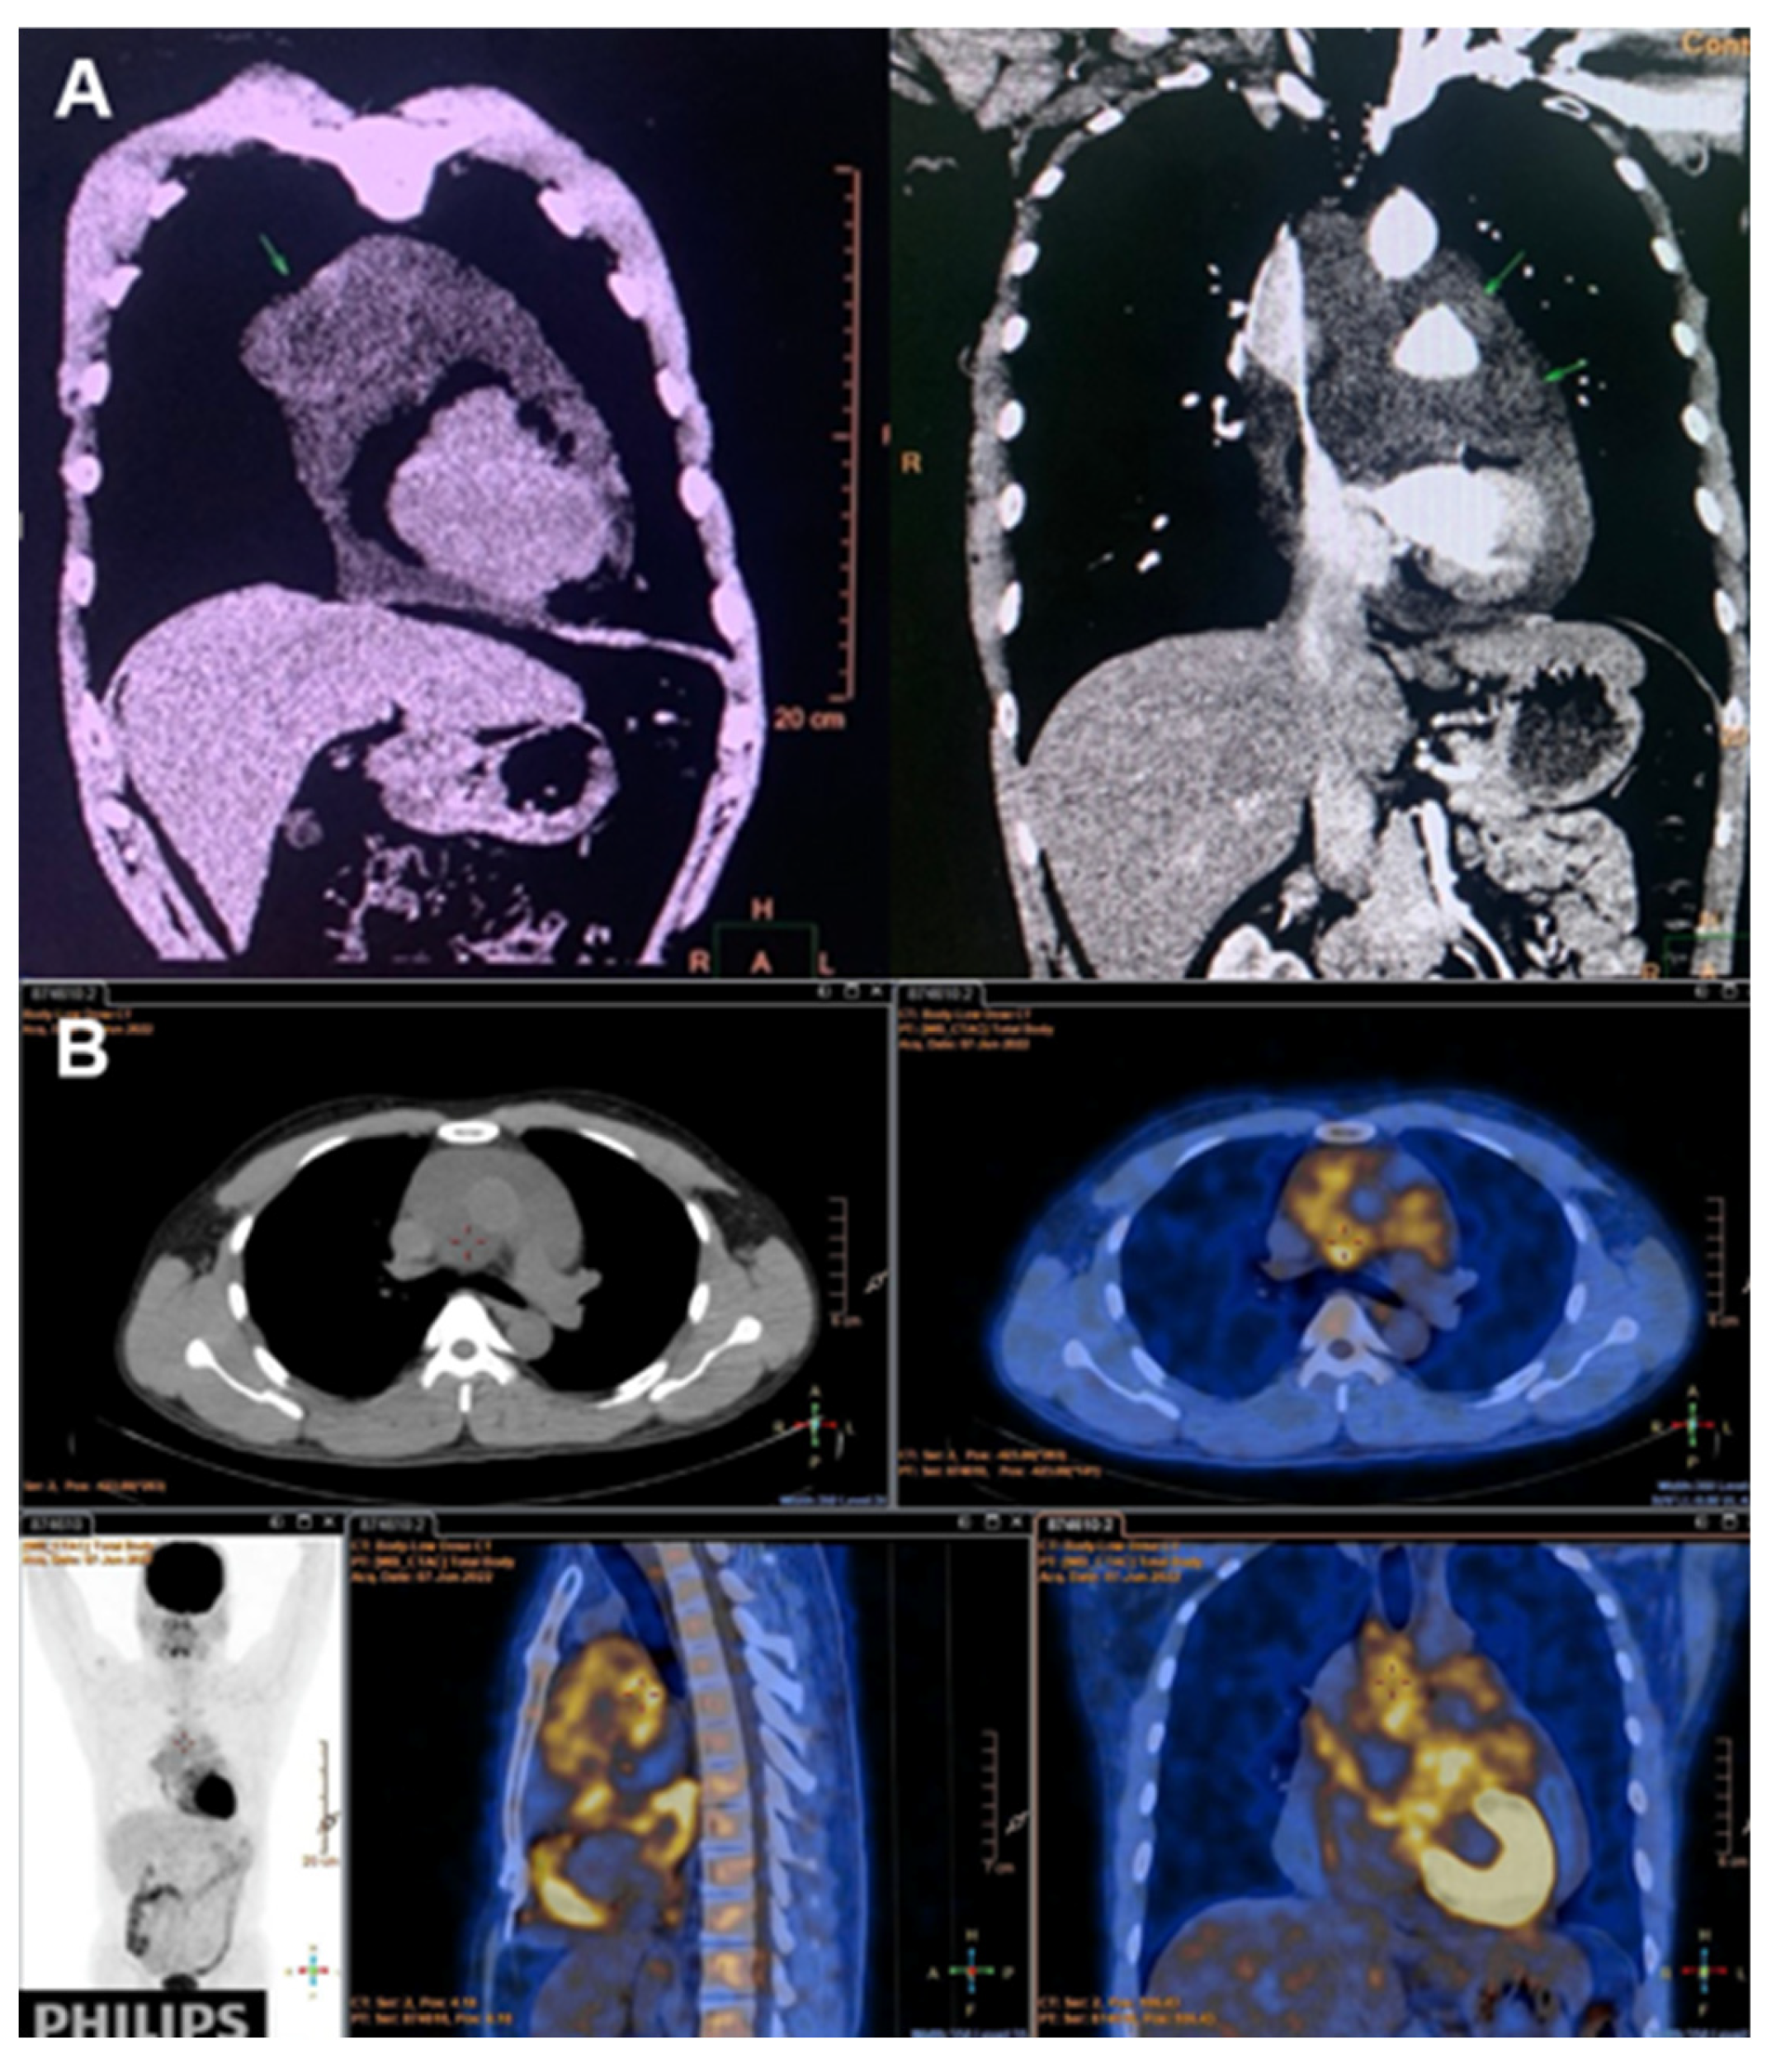

Subsequent cell-block analysis of pericardial fluid revealed epithelioid cells with nuclear atypia. Immunohistochemistry demonstrated strong positivity for CK5/6, CK7, and Calretinin; moderate positivity for WT1; and negativity for TTF-1—findings consistent with pericardial mesothelioma. PET/CT revealed pericardial thickening with multiple FDG-avid nodules without evidence of distant metastasis (Figure 1A and 1B).

Figure 1. A. Image of pericardial tumor on CT scanchest coronal view (blue arrow). The mass appears as an irregular, hypodense lesion adjacent to the cardiac structures with infiltrative margins. B. PET/CT scan image demonstrating hypermetabolic activity in the pericardium with multiple FDG-avid nodules, consistent with malignant etiology without evidence of distant metastasis.

Conventional imaging techniques provide variable utility. Echocardiography typically reveals nonspecific findings including pericardial effusion or thickening [9]. PET/CT offers additional diagnostic value through identification of hypermetabolic lesions, as demonstrated in our case.